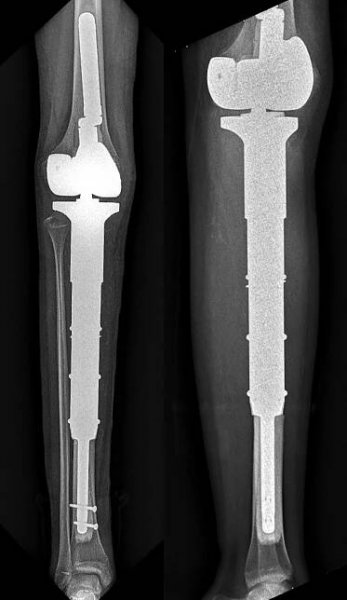

Pooperační RTG ukazující speciální krátký cementovaný dřík pojištěný dvěma interferenčními šrouby